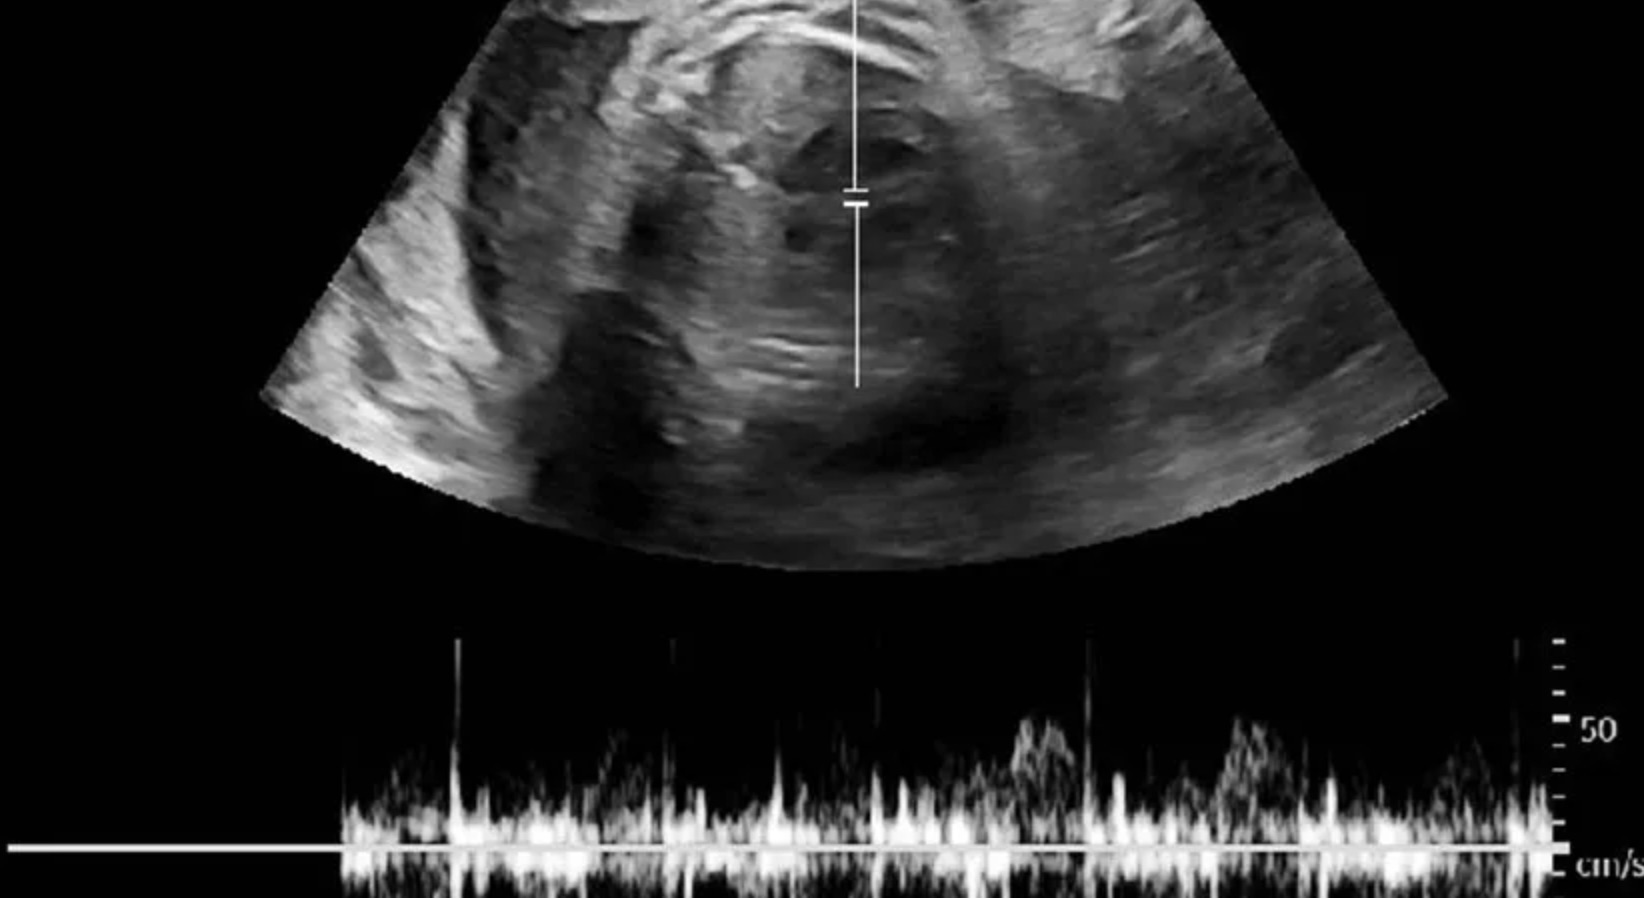

TPHCM - Đau đầu, phù chân, khó thở nhưng chị Thanh không biết mình mang thai cho đến khi bác sĩ siêu âm thai 34 tuần, dấu hiệu tiền sản giật.